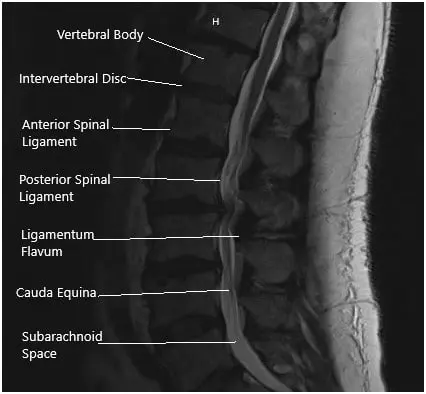

MRI suggested Ligamentum flavum hypertrophy contributing to severe central spinal stenosis at L2-L3. There was mild to moderate narrowing of the left neural foramen. There was a severe narrowing of the right neural foramen with effacement of the exiting right L2 nerve root due to a far lateral disc herniation.

At L3/4 there was a disc bulge and a facet and ligamentum flavum hypertrophy contributing to severe central spinal stenosis. There is mild to moderate narrowing of the bilateral neural foramina.

MRI of the Lumbosacral spine in sagittal and axial sections.